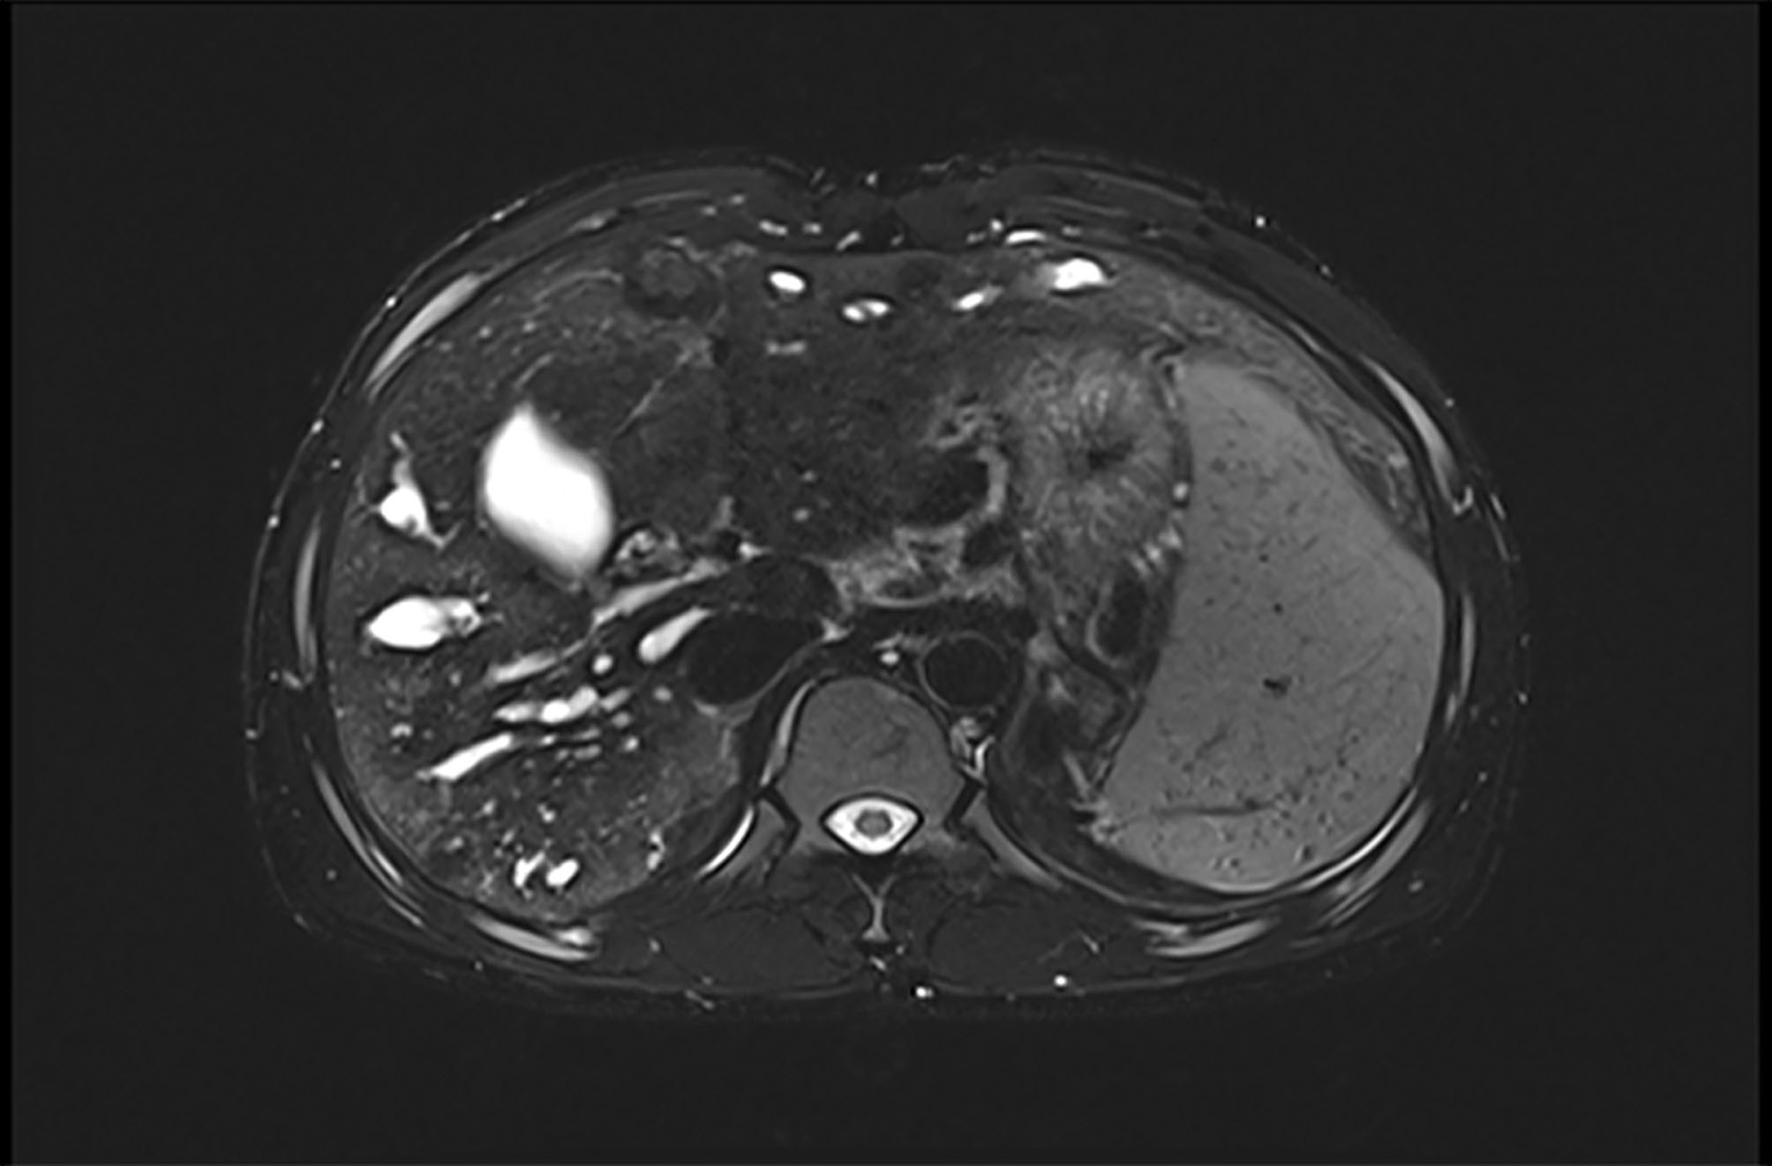

FIGURE 4

www.frontiersin.org

Figure 4. Hepatic MR shows the existence of liver nodule. MR, magnetic resonance.

At that moment, an amazing discovery was found by abdominal ultrasonography (US): his intrahepatic portal vein (PV) was absent, which seemed to be occluded (Figure 2A). To better understand this anatomic anomaly, we performed additional portal computed tomography angiography (CTA). It consistently delineated the dysplasia of the portal vein. There seemed to be two pathways for blood to flow in the main splenic vein (SV): one was in the portal vein that merged with the superior mesenteric vein and sent out a small branch into the liver (Figures 3A,B), whilst the other entered the inferior vena cava (IVC) via left renal vein. Also worth noting is that the hepatic artery was widened. Some regenerative nodules and abnormal hyperplasia nodules were visible. Liver magnetic resonance imaging (MRI) confirmed their existence (Figure 4).

AM is a congenital vascular malformation in the liver. Imaging shows that SMV and SV were fused in this patient and partially injected into the left renal vein, and there was a small portal vein running through the liver (Figures 2, 3). According to the classification proposed by Morgan and Superina (2), these features are classified as AM type II. To the best of our knowledge, AM rarely presents with syncope, and our patient is the first case of a male with CEPS (Abernethy II) showing syncope.

After analyzing all the reported cases (Table 1), excluding the population that lack the information about gender, it seems to be more common in men (1.2:1), especially type II (1.6:1). More than half of all published cases were diagnosed under the age of 18. Similarly, a report was found of a 15-year-old female patient with AM type Ib published 2 years prior (9). However, different from the demographic data collected in our review of the literature, the patient in this report was the first to be diagnosed with CEPS at 24 years old. Complications occurred in some patients (Table 1). In the reported cases, more than 20% of the patients had liver nodules, such as liver adenoma, hepatocellular carcinoma, focal nodular hyperplasia (FNH), and liver hemangioma. In the current case, abdominal CTA and liver MR also confirmed the presence of liver nodules. The proportions of cases with PAH and PH are 14.79% and 3.41%, respectively. In our case, the pulmonary hypertension may be related to the shunting of vasoactive substances in the portal vein. In recent years there were some incidental cases diagnosed with atypical clinical manifestations. The clinical manifestations of AM are diverse, and there are also some rare clinical manifestations, such as those with nephrotic syndrome (10) as the primary manifestation, or endocrine diseases such as hyperinsulinemia (1113). In addition to the atypical manifestations above, there were two patients previously reported to experience syncope (11, 14).